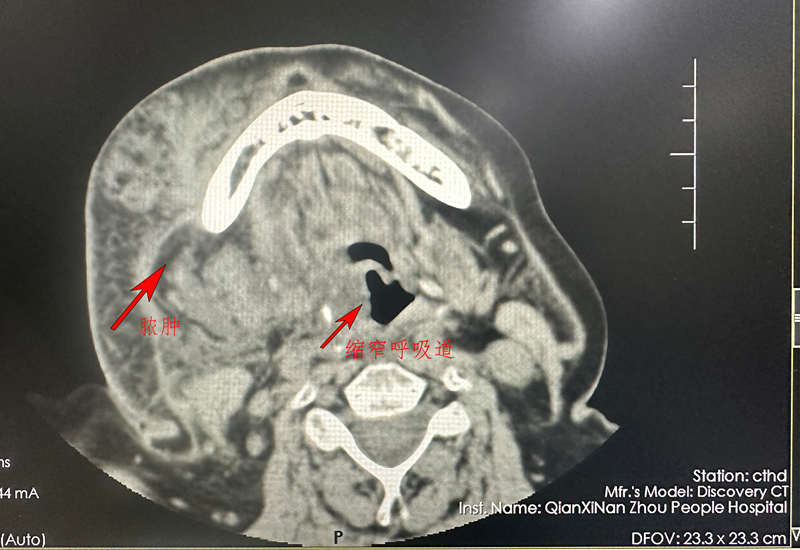

李阿姨,既往有糖尿病史、高血压病史,在3个月前发现反复的牙痛,在当地抗感染输液后依然感觉疼痛肿胀无减轻,甚至加重。遂来到我院口腔科就诊,通过影像检查发现该为患者已经出现口底多间隙、颈前间隙、纵膈感染,感染已经累及颈部、纵膈,导致相应气管狭窄,患者呼吸困难,有生命危险!

患者入院后,口腔科团队对此病例展开充分的术前讨论。口腔科主任王忠表示,传统的手术方案是行切开引流后使用引流管引流,考虑到患者目前情况严重,管状引流可能效果不佳,决定采取广泛切开引流后使用负压创面引流的手术方案。在征得患者及家属同意后,王忠主任团队为患者实施了全麻VSD装置植入术,半月后患者病情稳定,恢复快速,术后无明显并发症。